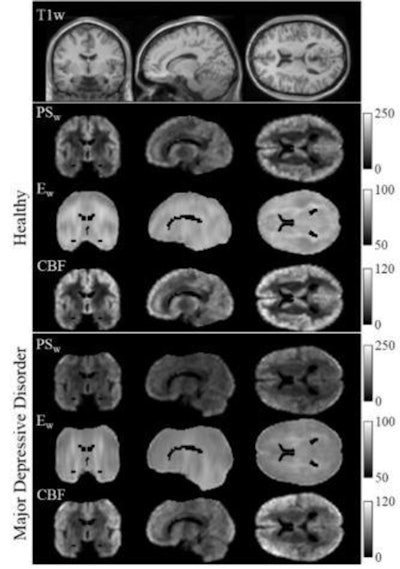

In the first study, co-author Wengler and colleagues from Stony Brook University in Stony Brook, NY, evaluated their newly developed MR imaging technique called intrinsic diffusivity encoding of arterial labeled spins (IDEALS), which targets the blood-brain barrier and the movement of water out of the blood vessels and into the brain tissue.

A total of 14 patients with major depressive disorder and 14 healthy control subjects underwent MRI brain scans using the IDEALS protocol. The images showed less water moving from inside the blood vessels to the outside in patients with the disorder, which would indicate a disruption in blood-brain barrier integrity. This difference was particularly significant in the gray matter regions of the amygdala and the hippocampus, which are associated with emotions and memory, respectively.

"We observed disruption of the blood-brain barrier in gray matter regions known to be altered in major depressive disorder," Wengler said. "This study helps improve our understanding of the pathophysiology of depression and can open new avenues of treatment for a disorder that affects over 100 million individuals worldwide."